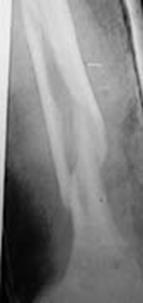

Fracturi simple: SPIRALA OBLICA TRANSVERSALA

Fractura spirala de Fractura transversa de diafiza femurala Fractura spirala de diafiza tibiala

diafiza humerala

Fractura spirala de diafiza tibiala Fractura oblica de diafiza tibiala Fractura transversala de diafiza tibiala